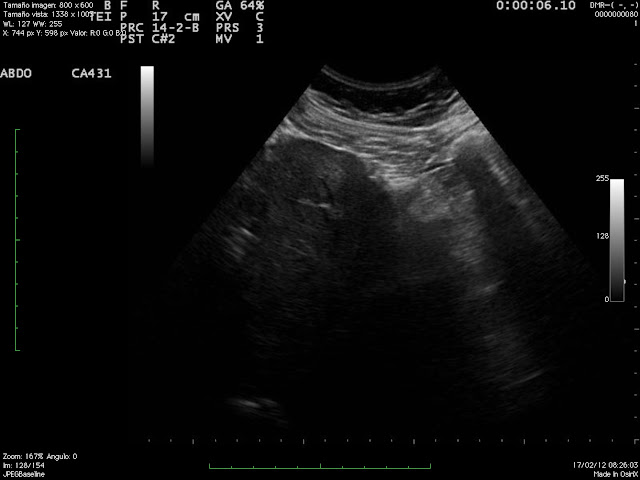

En control posterior aparecen estas imágenes. 1: Lesión hiperecógena en segmento 3 que respeta vaso sanguineo, compatible con esteatósis focal. 2: lesión hiperecógena - en segmento 5 - relativamente dishomogenea con halo hipoecógeno no vascularizada que presenta D.D. con hemangioma atípico y metástasis.

La R.M. confirma esta última posibilidad.

Video obtenido por vía intercostal